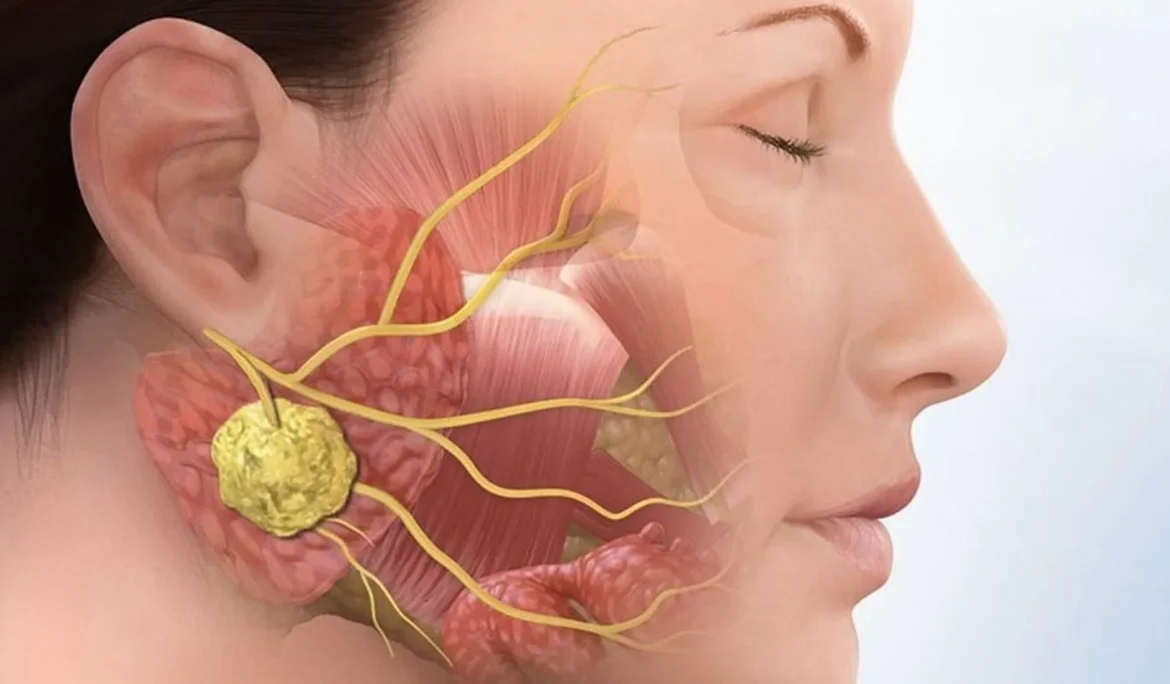

Răng mọc ngầm hàm dưới là vấn đề nha khoa phổ biến và phức tạp, nhất là với răng số 8 (răng khôn). Tình trạng gây đau